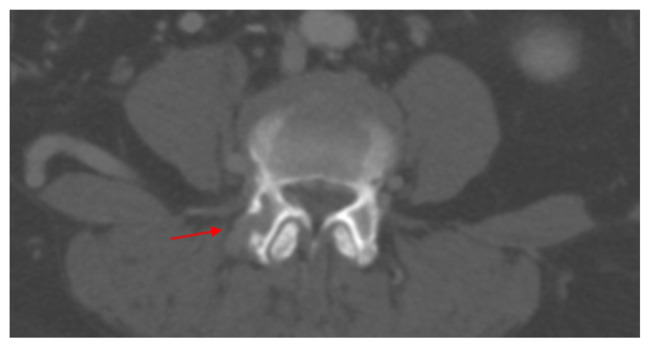

Pheochromocytomas and paragangliomas (PPGLs) are rare neuroendocrine tumors arising from adrenal medulla and extra-adrenal paraganglia. Metastatic pheochromocytomas, pose diagnostic and therapeutic challenges due to their atypical presentations and potential for malignant transformation years after primary tumor resection. We report a case of 61-year-old woman who presented with intermittent cough, shortness of breath, and elevated blood pressure 6 years after resection of primary adrenal pheochromocytoma. Imaging revealed bilateral pulmonary nodules, a retroperitoneal mass, and L4 vertebral involvement, raising suspicion for metastatic pheochromocytoma. Elevated serum meta-nephrines and normetanephrines, alongside tissue biopsy and MIBG imaging, confirmed diagnosis. Germline genetic testing did not reveal any pathogenic mutations. The patient underwent CT-guided cryoablation for retroperitoneal lymph nodes and scheduled for radiofrequency ablation (RFA) of metastatic lesions. This case underscores evolving understanding of PPGLs, challenging "10 % rule" regarding metastasis and inheritance. While mutations in genes such as SDHB are associated with increased metastatic risk, sporadic cases like this highlight need for lifelong surveillance in all patients' post-resection of primary tumor. Ablative techniques, EBRT, and emerging systemic therapies are promising methods for managing metastatic disease. This case highlights importance of long-term follow-up and genetic testing in patients with PPGLs, even in absence of hereditary mutations, to detect and manage late-onset metastatic disease efficiently.